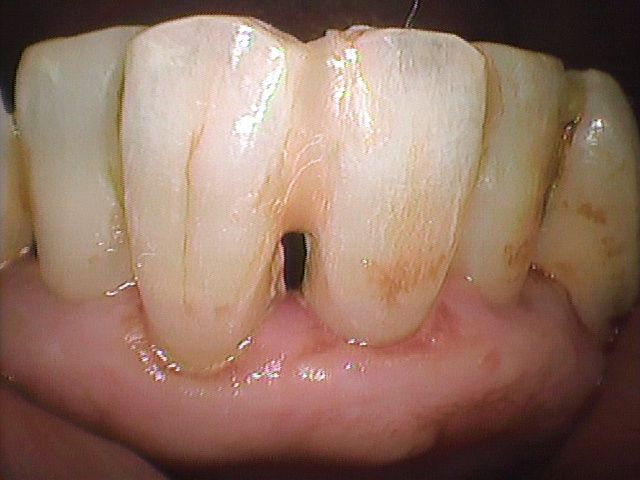

動揺歯を固定する方法は【仮固定と長期固定装置】があります。動揺歯を固定する方法はすでにBC6世紀に行なわれています(Photo-3) 21世紀の現代において、新しい技術でこれらの処置を適切な時期におこなうことによって動揺による歯周病の進行を改善し、歯の喪失を予防することは当然といえます。各々の方法については以下に詳しく述べます。